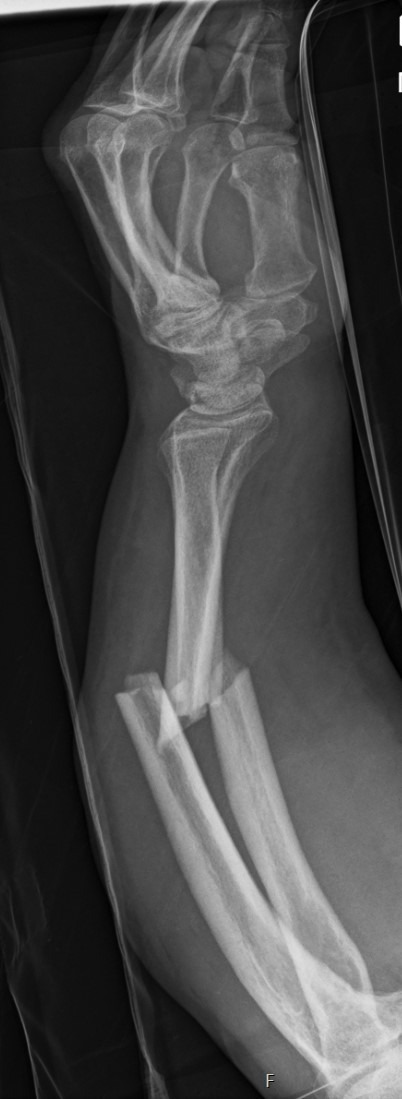

Röntgenbild eines Unterarmbruchs mit Fraktur von Speiche (Radius) und Elle (Ulna)

Röntgenaufnahmen eines Unterarmbruchs – vor und nach der Operation